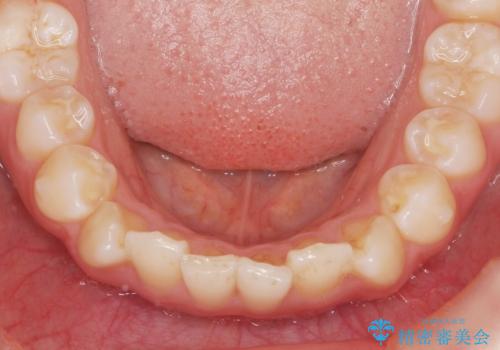

インビザラインライトで行う短期マウスピース矯正治療

- 前歯のガタつきを並べたいたいと、矯正治療を希望され来院されました。

とにかく短期間で前歯だけの治療を行いという希望が強く、全体矯正と前歯だけの部分矯正の仕上がりのイメージを確認したのち14枚のマウスピースで前歯のみの矯正治療を行っていくこととしました。

インビザラインライトは軽度なガタつきや傾斜の改善に用いられる全14枚のマウスピース矯正です。

短期間で治療の終了が見込めるだけでなく、料金もインビザラインフルに比べリーズナブルです。